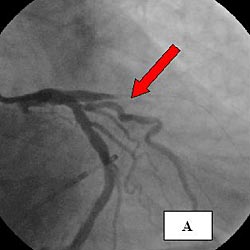

К этому времени пациент экстубирован, сознание восстановлено, при активном расспросе – ориентирован в местности и времени, ангинозный синдром и его эквиваленты отрицал. 30.08.08 в 11-00 в экстренном порядке выполнена коронарография, при которой выявлена острая окклюзия передней нисходящей коронарной артерии (ПНА, рис. 3 А).

Рис. 3. А - коронарограмма больного Б., 67 лет. Стрелкой показана острая окклюзия ПНА.

Б - восстановление кровотока по ПНА после реканализации и стентирования.

В экстренном порядке выполнена реканализация, тромбоэкстракция системой ANGIOJET и стентирование ПНА (рис. 3 Б), после чего пациент переведен в БИК. В раннем послеоперационном периоде регистрировались признаки реперфузионного синдрома в виде одиночных и парных монотопных желудочковых экстрасистол. Продолжена терапия по стандартам ведения ОКС с подъемом сегмента ST на ЭКГ, в первые сутки гемодинамика поддерживалась введением допмина в дозах 3-5 мкг/кг/мин.